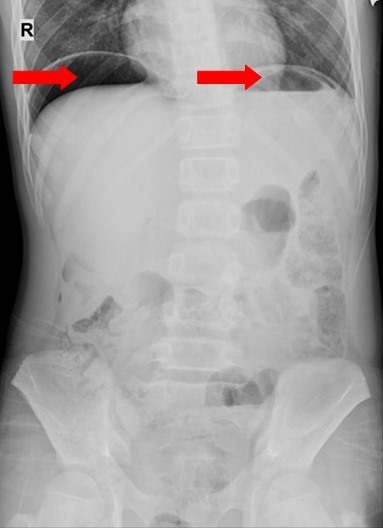

Hình ảnh phim chụp X-quang ổ bụng của bệnh nhi.

Gần đây nhất là trường hợp bệnh nhi Đ. T. D., 11 tuổi, địa chỉ tại Xã Hồng Phong, thị xã Đông Triều. Ngày 1/11/2020, sau khi ăn tối trẻ xuất hiện đau quặn bụng dữ dội quanh rốn, sau lan ra khắp bụng. Trẻ nôn 3 lần ra dịch tiêu hoá, được đưa đến cấp cứu tại Trung tâm Y tế thị xã Đông Triều, sau đó được chuyển Bệnh viện Việt Nam - Thuỵ Điển Uông Bí tiếp tục điều trị. Qua thăm khám và kết quả chụp X-quang bụng với hình ảnh thủng tạng rỗng, các bác sĩ đã chỉ định phẫu thuật nội soi cấp cứu cho bệnh nhi.